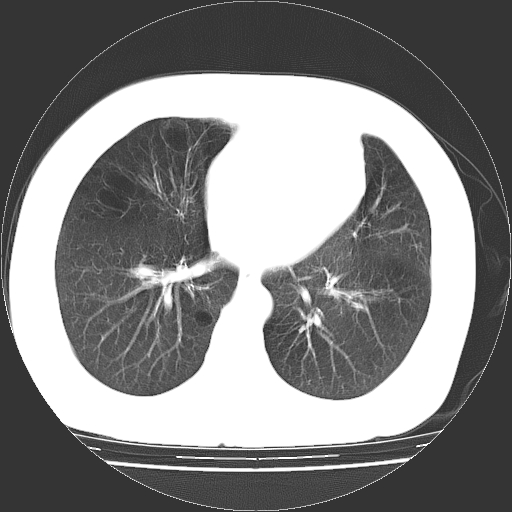

标题: CT13141:女,70岁,咳嗽、胸闷半个月。 [打印本页]

标题: CT13141:女,70岁,咳嗽、胸闷半个月。

女,70岁,咳嗽、胸闷半个月。纵隔窗未见异常,未上传。

1.小叶中心型肺气肿。

2.左肺下舌段感染性病变。

双肺多发肺大泡。